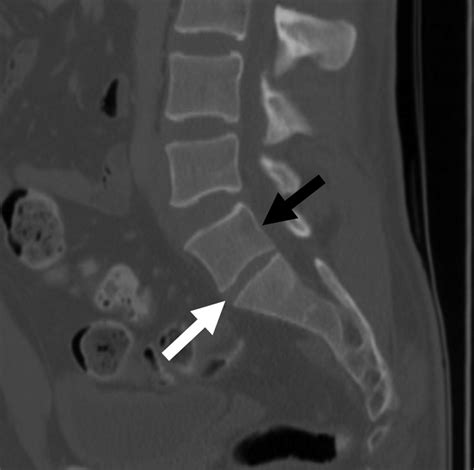

• CT Scans: Offer detailed images of the bone structure, helping to identify specific features of LSTV.